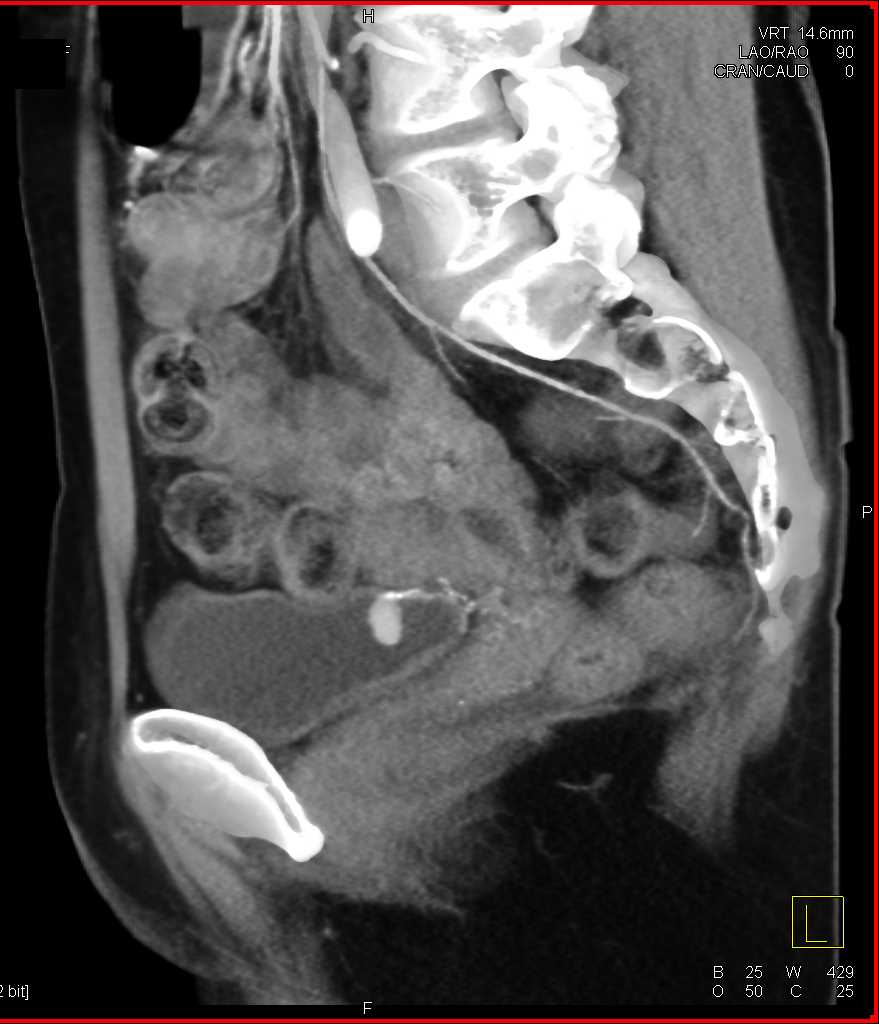

Bladder Cancer with Active Bleed